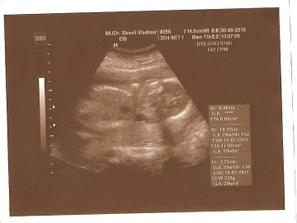

30.9.2010 - 3D ultrazvuk - velký ultrazvuk ve 20 tt

Krásně rosteme, vážíme přesně 339 g a dokonce krásně spolupracujeme k nafocení všech částí těla, co pan doktor potřebuje.

Zatím to nevíme na 100 %, ale vypadá to, že čekáme chlapečka !